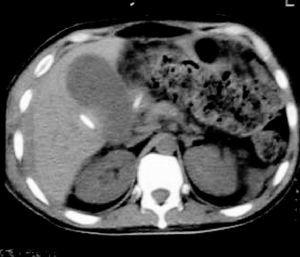

Paciente de 34 años de edad, sin antecedentes médicos de interés, que acude al hospital por un cuadro de abdomen agudo como consecuencia de una apendicitis flegmonosa retrocecal ascendente, que fue intervenida quirúrgicamente en las siguientes 12 horas tras el ingreso hospitalario. Tres días más tarde, el paciente presenta dolor de tipo cólico en hemiabdomen inferior y diarrea. Al examinarlo el abdomen está tenso, distendido, y con aumento de los ruidos hidroaéreos. Fue diagnosticado de evisceración encubierta y se realizó una enterolisis por bridas y plástica de pared abdominal. Diez días después de esta intervención, se observó un débito purulento por la herida quirúrgica, fiebre, aumento del dolor abdominal y nueva evisceración. En el quirófano se encontró una peritonitis purulenta por perforación del íleon a 50 cm de la válvula ileocecal, y una fístula enterocutánea. Se realizó resección intestinal, anastomosis entérica término-terminal y se dejó un drenaje frente a la anastomosis. El paciente ingresó en la Unidad de Cuidados Intensivos en el postoperatorio inmediato, presentando los siguientes signos vitales: presión arterial 110/70 mmHg, frecuencia cardíaca de 138 latidos por minuto (lpm), frecuencia respiratoria de 26 respiraciones por minuto (rpm), temperatura axilar 35,2 ºC, Glasgow coma score 15. La analítica mostraba los siguientes resultados: hematocrito 32,3%, hemoglobina 9,7 g/dl, leucocitos 13.800/mm3, plaquetas: 378.000/mm3, tiempo de protrombina 73%, tiempo de cefalina 62 segundos, glucosa 1,22 g/l, urea 0,45 g/l, creatinina 0,71 g/l, sodio 134 mEq/l, potasio 4,4 mEq/l, calcio total 8,51 mg/dl, bilirrubina total 2,8 mg/dl, bilirrubina directa 2,1 mg/dl, proteínas totales: 5,46 g/dl, albúmina 3,01 g/dl. Se inició tratamiento antibiótico con metronidazol, ampicilina y gentamicina, soporte inotrópico con noradrenalina y oxigenoterapia. A las 72 horas de evolución el enfermo persistía séptico, sin aislamiento de microorganismos en los cultivos y con distensión y dolor abdominal e intolerancia digestiva. Una ecografía abdominal mostró una colección subhepática residual y se decidió realizar el drenaje de la misma por vía percutánea. Tras el drenaje el paciente evolucionó con agravamiento del estado general, hipotensión arterial, taquicardia, taquipnea, signos de mala perfusión periférica, oliguria, sangrado pericatéter y un gran hematoma (15 x 15 cm) en hipocondrio y flanco derecho. Una nueva analítica mostró un tiempo de protrombina del 90% y de cefalina de 107 segundos y un recuento plaquetario de 286.000/mm3. Tras la transfusión de 4 unidades de glóbulos rojos desplasmatizados y de plasma fresco congelado, el tiempo de protrombina era del 85%, el tiempo de cefalina de 76 segundos, el tiempo de Ivy 5 minutos, y el recuento de plaquetas 300.000/mm3. Se realizó una determinación de factor VIII con un resultado del 5% (valores normales: 50-150%) y que no se corrigió con plasma, diagnosticándose la presencia de factor inhibidor circulante. No se pudo determinar la concentración del mismo. La presencia de una alteración del tiempo de cefalina que no se corrige con el agregado de plasma normal y la presencia de bajos niveles de factor VIII circulante se consideraron diagnósticos de hemofilia adquirida, por lo que se inició un tratamiento inmunosupresor con metilprednisolona 60 mg/día, transfusión de plasma fresco congelado y varias unidades de glóbulos rojos, pero ante el fracaso de la terapéutica se agregó ciclofosfamida en dosis de 100 mg/día y terapia sustitutiva con 3.600 U de factor VIII cada 8 horas. A las 48 horas de tratamiento el paciente no presentaba signos de sangrado, pero continuaba con un tiempo de cefalina de 86 segundos y un tiempo de protrombina del 80%. Se inició tratamiento con gammaglobulina 1,5 g/kg en infusión durante 48 horas y rFVIIa 90 µg/kg cada 2 horas. A las 12 horas de este tratamiento el paciente sufrió un episodio de hipotensión arterial y descenso de la hemoglobina hasta 5,1 g/l, con persistencia de la coagulopatía (tiempo de protrombina 56% y tiempo de cefalina 54 segundos), por lo que se inició tratamiento con vitamina K parenteral, se cambió el tratamiento antibiótico a imipenem y vancomicina y se realizó una nueva tomografía axial computarizada (TAC) de abdomen (fig. 1), donde se observó un importante hematoma organizado en la zona peritoneal. El paciente fue llevado de nuevo al quirófano, donde se realizó un drenaje del hematoma. Pasadas 72 horas el paciente se encontraba afebril, hemodinámicamente normal, con un abdomen menos distendido, blando y depresible y tolerando nutrición enteral. En la analítica presentaba un recuento plaquetario de 240.000/mm3, tiempo de protrombina del 92% y tiempo de cefalina de 46 segundos, por lo que fue dado de alta de la UCI, permaneciendo en el hospital por espacio de dos meses sin recidivas hasta el alta hospitalaria.

Figura 1. Se observa en el flanco derecho una lesión heterogénea con zonas hipodensas en su interior que corresponde a restos hemáticos. La lesión se encuentra limitada por una pared que podría corresponder al epiplón y/o mesenterio.